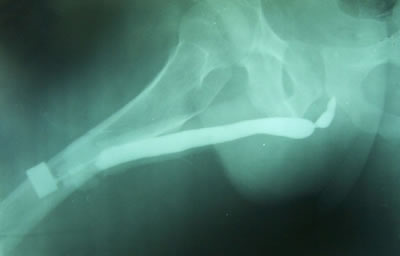

Медицинские исследования: уретрография и цистография